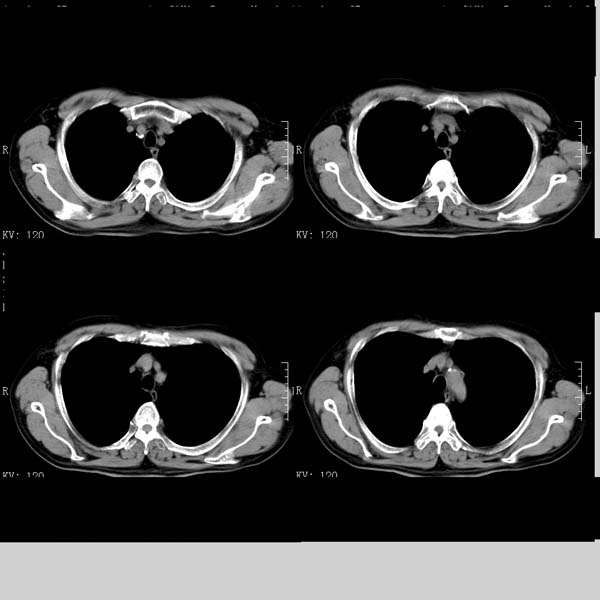

以下是引用守望可可西里在2008-6-24 1:11:00的发言:[br][br] 考虑为周围型肺癌:[br] 1.分叶结节,形态极不规则,蟹足样伸展的恶性浸润特征比较明确。[br] 2.磨玻璃影中由多个更高密度小结节聚集呈梅花瓣样。[br] 3.局部胸膜凹陷征比较明确。[br][br] 另:纵隔胸膜明显增厚、粘连。

以下是引用zjzjr在2008-6-24 11:19:00的发言:[br]支持左下肺周围型肺癌伴右肺转移,纵隔淋巴结转移,心包积液.

以下是引用zhangling在2008-6-24 14:56:00的发言:[br]我们科室意见报告为[br][br]1考虑左下肺周围型肺癌[br]2右肺小结节考虑转移瘤,纵隔淋巴结转移[br]3心包积液. [br] 各位老师分析的相当好 谢意[br]